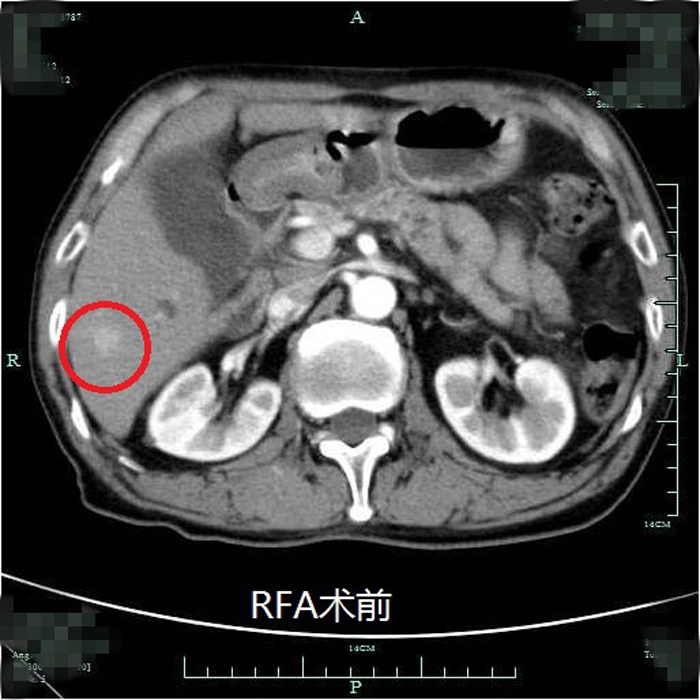

典型射頻治療患者術(shù)前術(shù)后效果對比(非該尾狀葉患者)